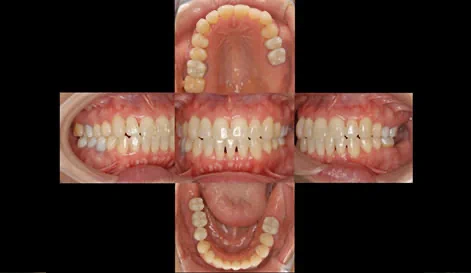

以前より右下の銀歯が度々悪くなり、今回右下の歯ぐきが大きく腫れてしまった患者様です。

注目する点は、前歯がしっかり噛み合っていないことです。

患者様も食べ物をしっかり噛めないと感じていました。